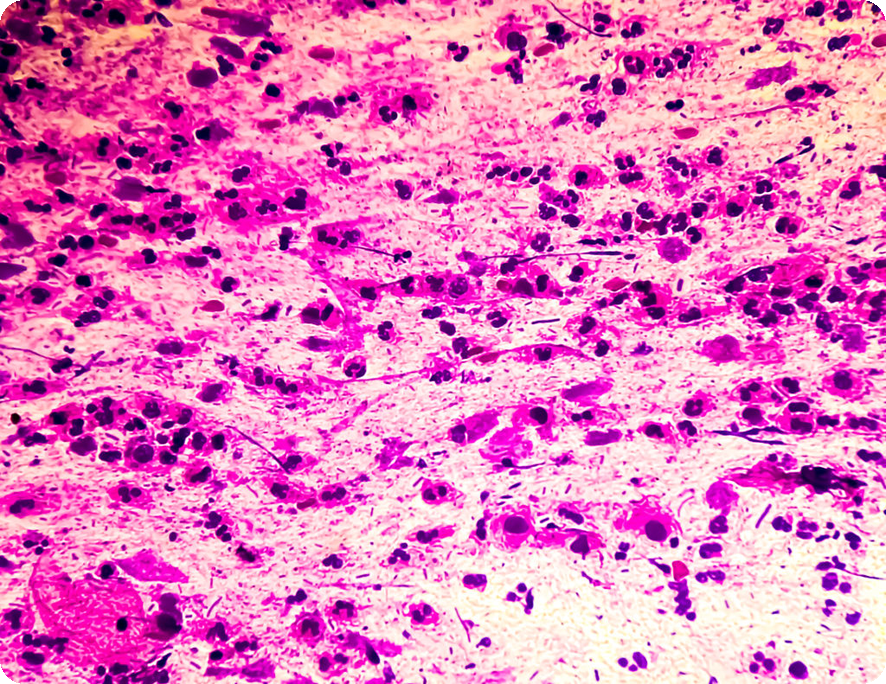

심장사상충(Dirofilaria immitis)는 실 모양의 기생충으로, 특히 개와 고양이에게 위험한 질병을 일으킵니다. 이 기생충은 주로 동물의 심장 및 폐동맥에 기생하며, 감염이 진행되면 심각한 건강 문제를 초래할 수 있습니다. 감염된 개의 심장이 손상되면, 결국에는 치명적인 결과로 이어질 수 있습니다. 심장사상충은 식육목 동물에만 생존하며, 인간에게도 감염될 가능성이 있지만 치명적인 결과를 초래하지는 않습니다.